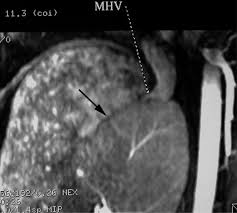

Chiasmata -mə-tə or chiasmas also chiasms 1. Esophageal varices are extremely dilated sub-mucosal veins in the lower third of the esophagus. Located in metro Denver northern Colorado and western Nebraska serving all of the Front Range our team consists of board-certified and fellowship-trained interventional radiologists. This results in hepatic congestion similar to Budd-Chiari syndrome and post-sinusoidal portal hypertension. The patients condition should be monitored throughout the procedure. They are most often a consequence of portal hypertension commonly due to cirrhosis. Toxic injury to liver sinusoids causes sloughing of endothelial cells that embolize to hepatic venules and cause eventual fibrosis of the venules. Coin in the Esophagus. There is no clear consensus regarding the number of occluded veins some authors claim that there should be at least one occluded hepatic vein 7 others state that there are no significant.